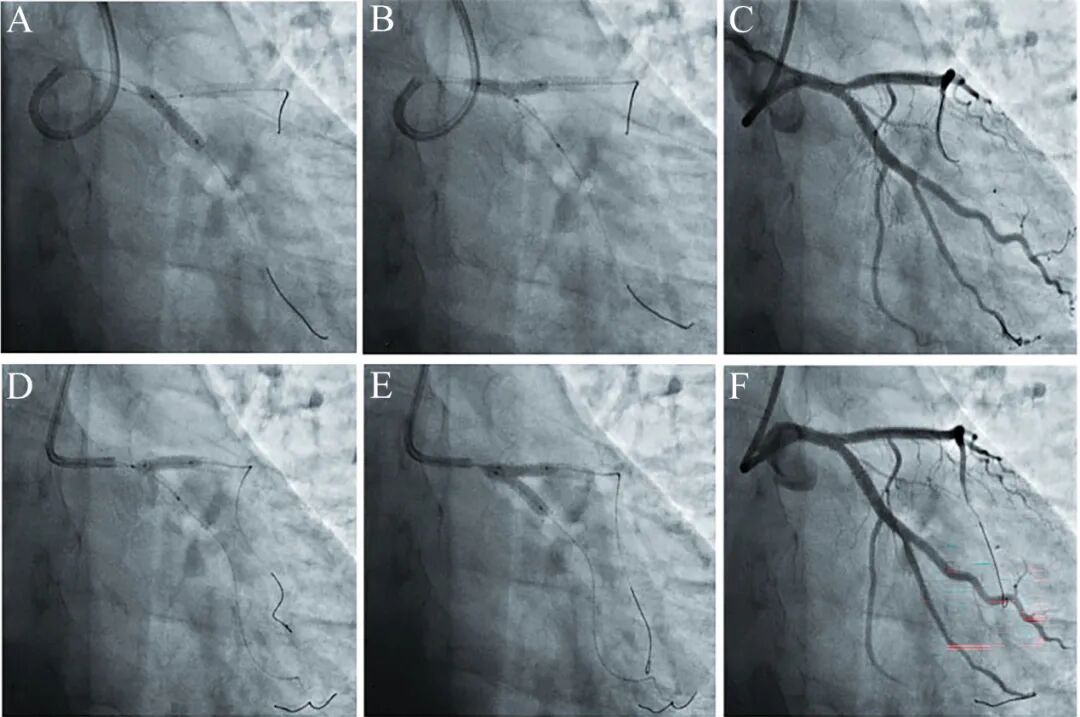

图7 回旋支开口花瓣技术[4]

再一次体外组装支架球囊复合体,送至回旋支开口。先回旋支支架释放(A),然后前降支锚定球囊扩张(B),最后支架球囊再次扩张。造影发现前降支开口受影响(C)。最后采用NC球囊对吻扩张(D-E),结果良好(F)。